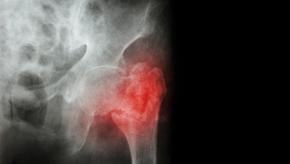

Osteoporosis is a major public health problems and is associated with a high burden of fractures and subsequent increased mortality.